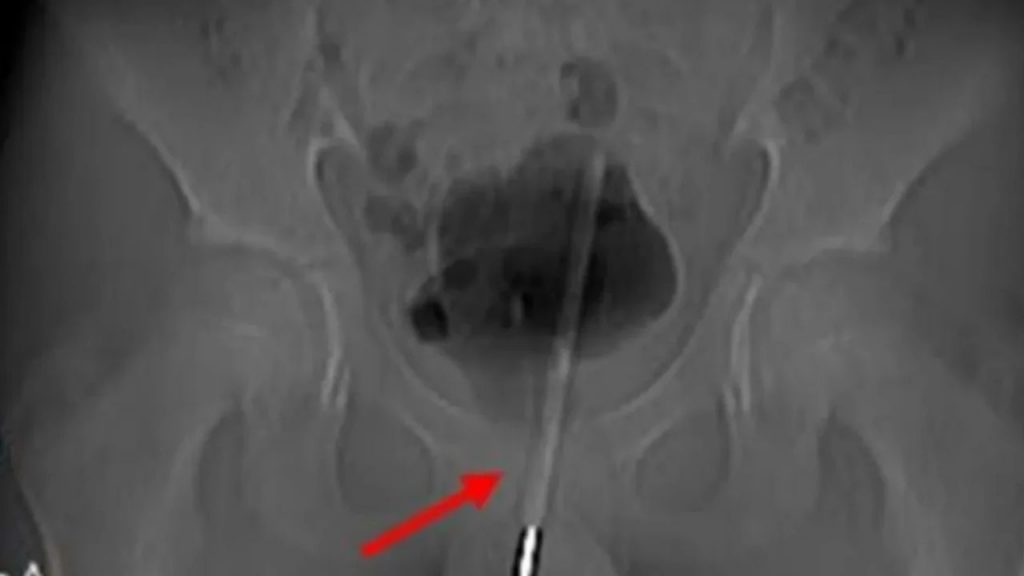

Tras el intensó dolor, el menor fue intervenido en urgencias, y a través de un examen de rayos X, el objeto se introdujo desde el tracto urinario, hasta llega a la vejiga.

Los urólogos decidieron operar al menor atravesando su vejiga, para que este no perdiera su parte intima.